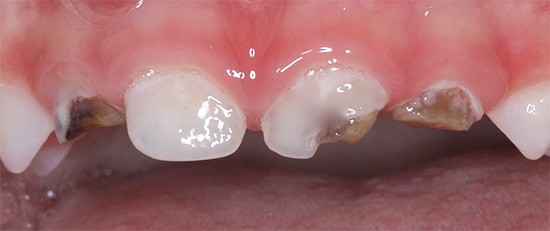

Foto dei denti con carie in bottiglia prima e dopo il trattamento:

Più avanti nella foto - carie media, che copre più denti contemporaneamente. Una tale lesione simultanea è un segno diagnostico caratteristico della carie in bottiglia:

Di norma, la carie di bottiglia colpisce prima i quattro denti superiori anteriori del bambino. Il processo cariato spesso inizia nella zona gengivale, copre rapidamente l'intero dente attorno alla gengiva lungo il perimetro e penetra negli strati profondi di smalto. Il danno alla zona gengivale del dente è una caratteristica della carie in bottiglia.